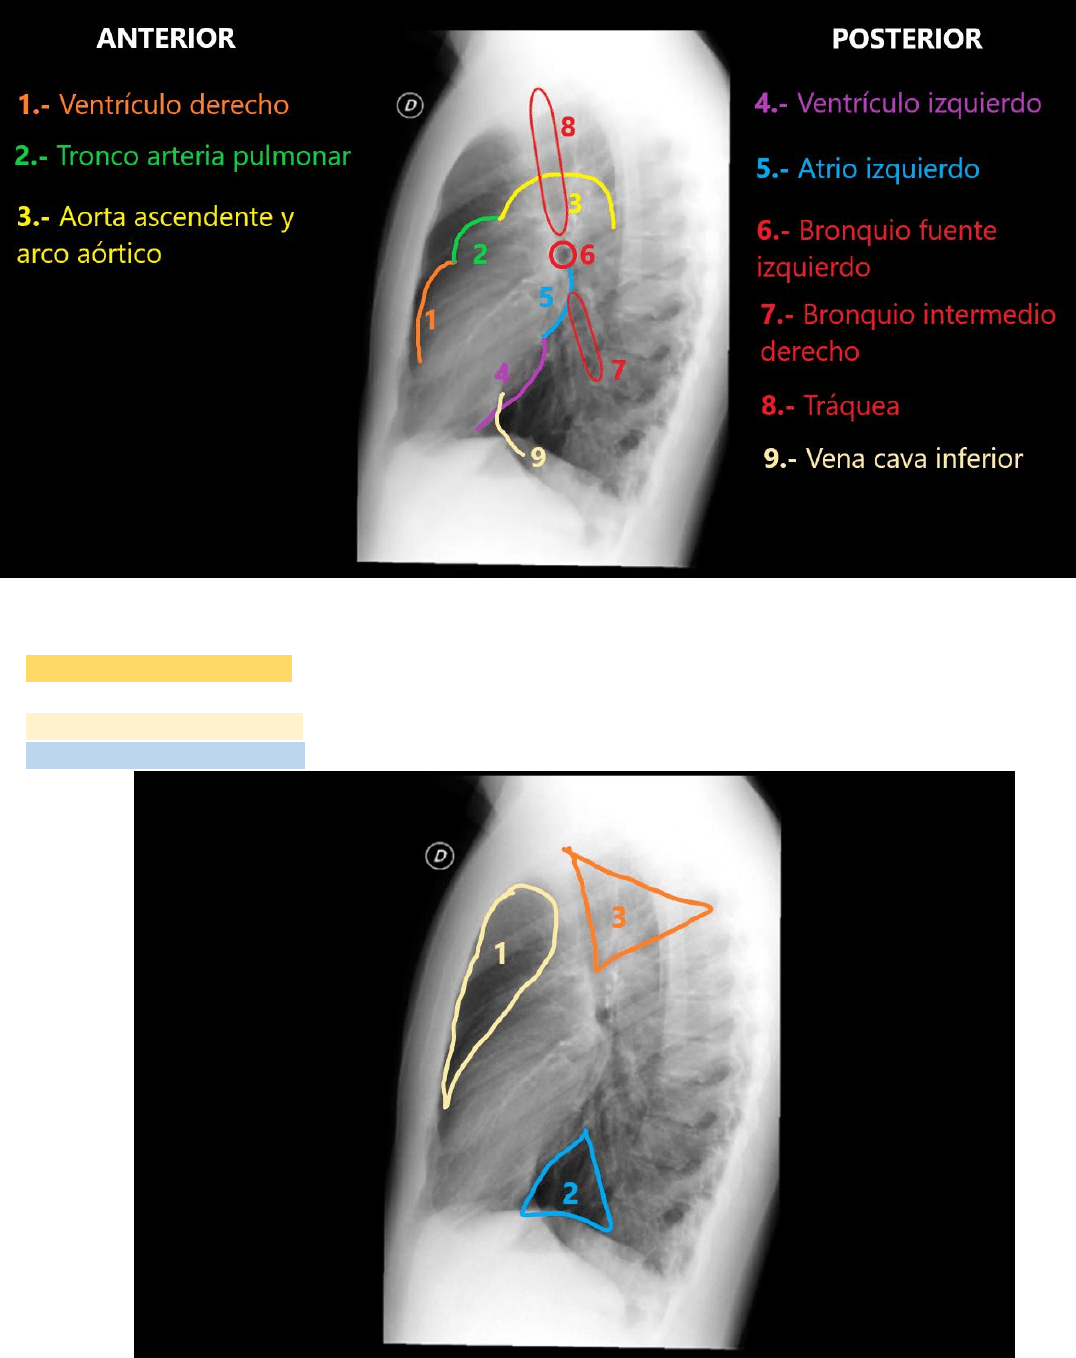

En la radiografía de incidencia de perfil también se ven estructuras mediastinales que están en contacto con parte del

parénquima pulmonar aireado.